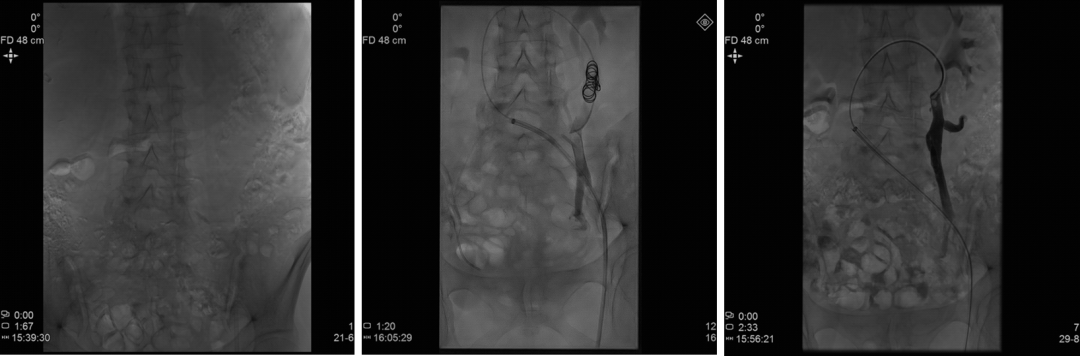

介入治疗技术演进

同轴技术

可调弯鞘+Cobra2导管+微导管

传统三明治技术(sandwich)

弹簧圈+泡沫硬化剂

大于目标血管(>2mm)1-3mm

静脉造影+Valsalva maneuver

Ovarian/Internal iliac/Vulvar/Vaginal Varicosities

Sandwich技术优化-节约版

GLUBRAN替代Onxy;

双股静脉入路:可调弯鞘解决反流支;

节约型三明治技术--中山三板斧